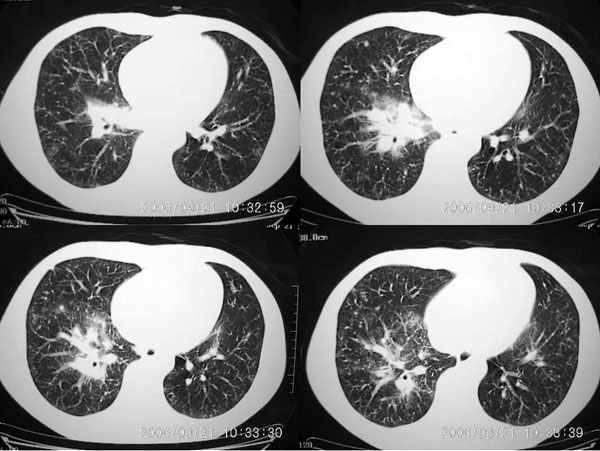

男 27岁 咳嗽一个月,治疗无效。

两肺弥漫均匀分部粟粒壮影 右肺基底段不规则软组织密度影其内密度不均 纵隔内淋巴结钟大 请进一步右肺病灶薄层检查及补充病史后再会诊

两肺弥漫均匀分部粟粒壮影 右肺基底段不规则软组织密度影其内密度不均 纵隔内淋巴结肿大,考虑间质性炎变。不除外职业病改变

右肺下叶后基底段结节样病灶,边界不规则,密度不均,右肺门团片影,肺门增大,纵隔见肿大淋巴结.结合临床首先考虑:肺结核.

图像显示:右下肺门增大,伴右下肺斑片状高密度影,密度不均;右下肺支气管管壁增厚,纵隔内淋巴结肿大。意见:支气管内膜结核、结节病。建议行纤支镜检查。

右下肺脊柱旁结节样肿块,可见毛刺,右侧肺门影增大,并见气管隆突前、主动脉窗内多发结节影。

右肺门影增大,纵隔内可见多个淋巴结肿大,右肺下叶内后基底段斑片状模糊影,两肺间质性改变;考虑右肺内结核并右肺门及纵隔淋巴结结核可能性大;职业病及结节病待排;肿瘤不太支持,年龄轻,无咯血,未见明显支气管狭窄,建议穿刺活检。

右下肺后基底段病灶虽然具有周围型肺癌的一些征象,但是它太虚了,纵肺比例过小,不到50%。而且在纵隔窗也显示该病灶比较虚,“块儿”比较小,内部也不实在,有小泡。

单就此病灶来说,考虑结核更为妥当。但问题是右肺门以及纵隔多组淋巴结肿大不太好解释,再有就是双肺的粟粒病灶,如果是血播的话应该有很明显的症状、体征的,不至于象楼主这般轻描淡写。

肺部有这么多病灶,临床症状却不多,我认为首先应该考虑:细支气管肺泡癌。

m 27 右肺门影增大,纵隔内可见多个淋巴结肿大,右肺下叶内后基底段斑片状模糊影,两肺间质性改变;考虑结节病或结核,建议纤维支气管镜穿刺活检.鉴别诊断1;淋巴瘤,纵隔淋巴肿大(胸骨后淋巴肿大突出)进展快,范围不够大,无融合及包埋改变..2结核其淋巴结密度是不均匀的,其内部一般有干酪坏死.可有钙化.可做ppd试验进一步明确.3结节病往往表现为肺门淋巴结对称性肿大.